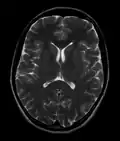

Normal axial T2-weighted MR image of the brain -